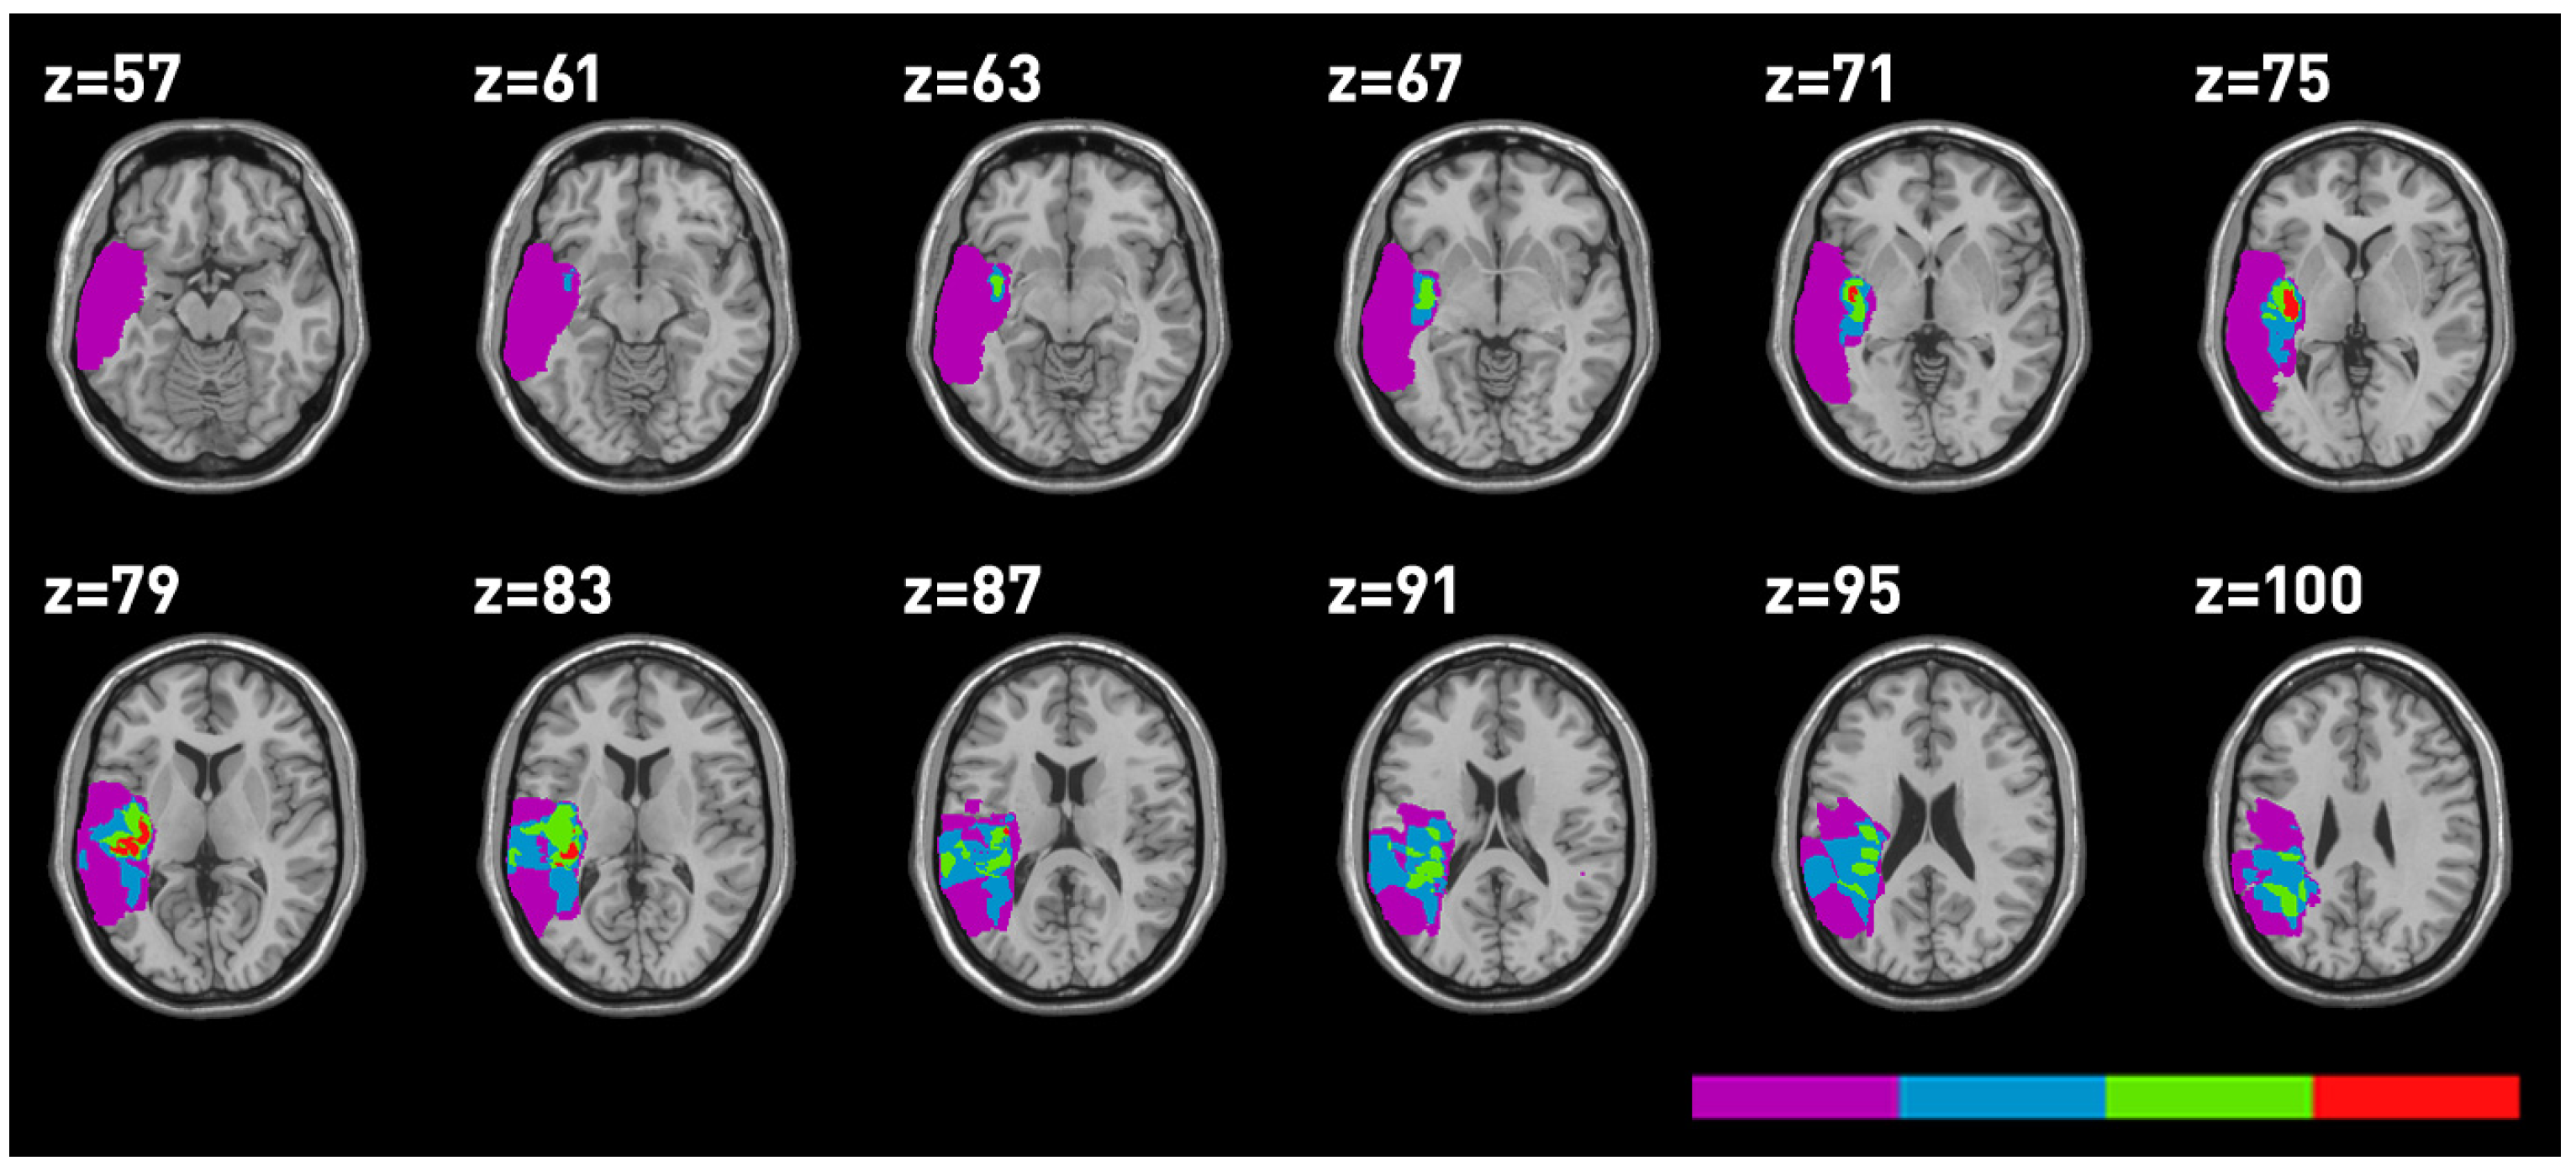

3. Lesion Mapping

Lesions were mapped using MRIcro on 17 MRI performed at the time of testing. Five MRI were unavailable. The anatomical sites, which proved to be involved in the lesion for all patients are reported in

Table 5 and the lesion mappings are reported in

Figure 3,

Figure 4. The superior temporal gyrus (STG), the MTG and the insula were the sites of major overlapping in temporal LBD as well as RBD patients.

Figure 3.

Mapping of the areas involved in RBD. Different colours correspond to the degree of lesion overlapping, with red indicating the region involved in all patients.

Figure 3.

Mapping of the areas involved in RBD. Different colours correspond to the degree of lesion overlapping, with red indicating the region involved in all patients.

Figure 4.

Mapping of the areas involved in temporal LBD.

Figure 4.

Mapping of the areas involved in temporal LBD.